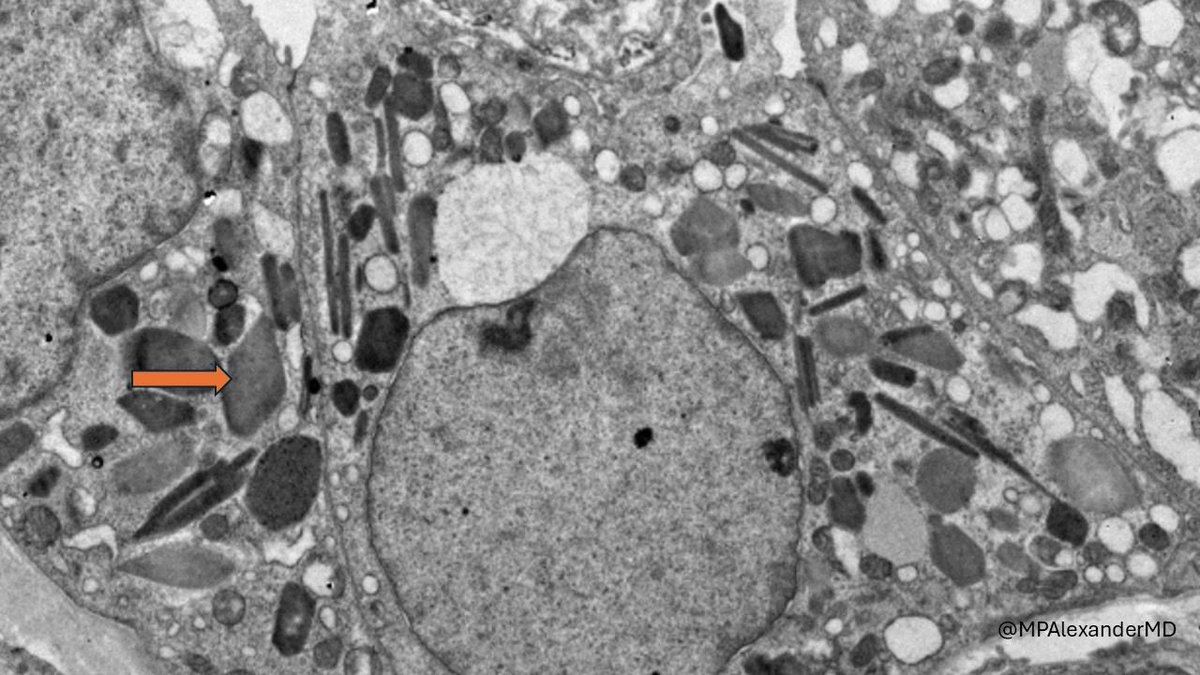

Mini case-series of crystal-storing histiocytosis (CSH) affecting predominantly glomerular loops with detailed literature review of renal CSH, images of one of the cases are depicted below, authors.elsevier.com/c/1Zh4S3uV~y8B…